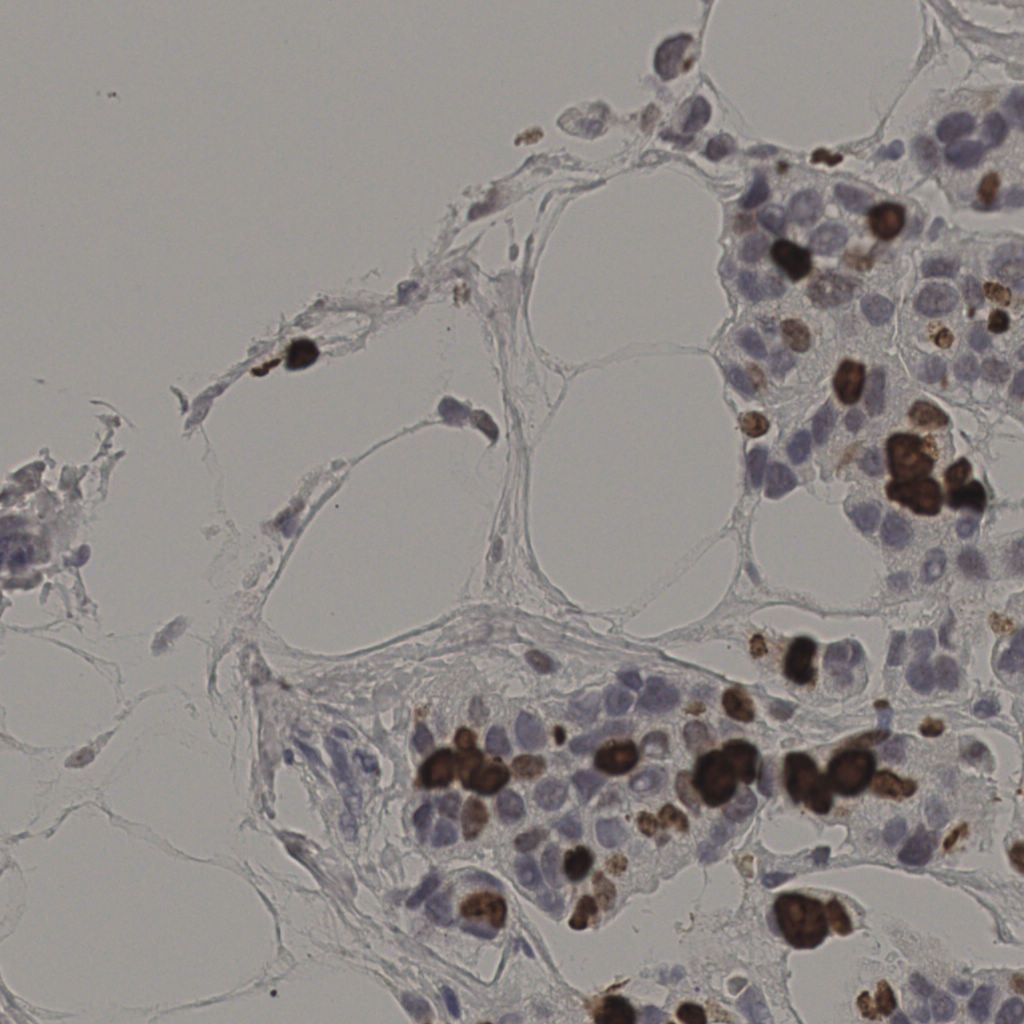

17.75%

Ki67 指数

阴 7986 阳 1723

总切片 2640

有效 412

已标记 412

有效率 16%